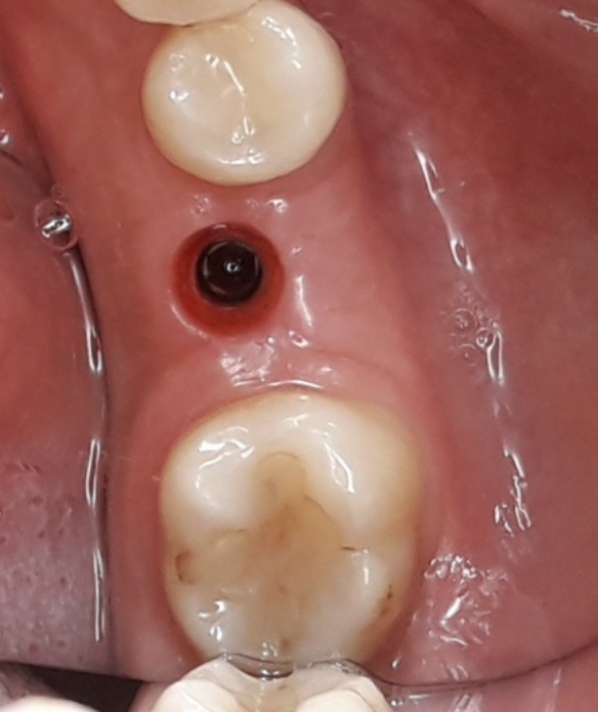

La tecnica denominata M.T.G. (Matrix Tissue Graft) si basa sull’utilizzo di una particolare matrice dermica acellulare riassorbibile di origine suina caratterizzata da un elevata consistenza e stabilità volumetrica che viene posizionata al di sotto del lembo muco periostale eseguito a spessore totale, in contatto con la cresta ossea. La stabilizzazione della matrice avviene senza mezzi di fissazione o in casi limitati mediante l’ausilio di una sutura riassorbibile con cui ancorare la matrice al lembo mucoperiosteo.

Nello studio sono stati inclusi 20 pazienti (12 donne e 8 uomini) di età compresa tra i 28 e i 65 anni, con edentulia singola e conseguente deficit vestibolare dei tessuti molli. La matrice dermica a elevata consistenza è stata opportunamente ritagliata mediante forbici e lama ed è stata posizionata al di sotto del lembo muco periostale allestito con approccio a spessore totale, vestibolarmente alla cresta ossea in cui è stato posizionato contestualmente un impianto endosseo osteointegrabile. Non si è utilizzato alcun ausilio di fissazione per la matrice dermica che è stata stabilizzata dal solo lembo di accesso ribaltato su di essa e suturato, mediante punti staccati semplici, al lembo linguale.